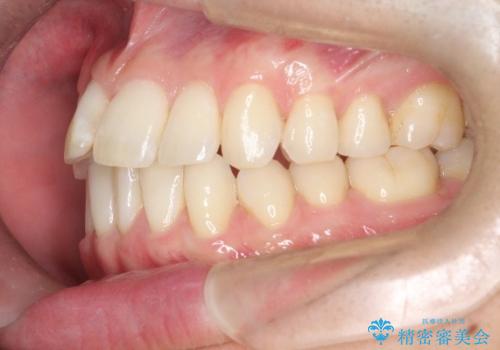

前歯の重なりとガタガタをマウスピースで改善した症例

見た目、嚙み合わせ及び、治療期間や施術内容に大変ご満足いただきました。